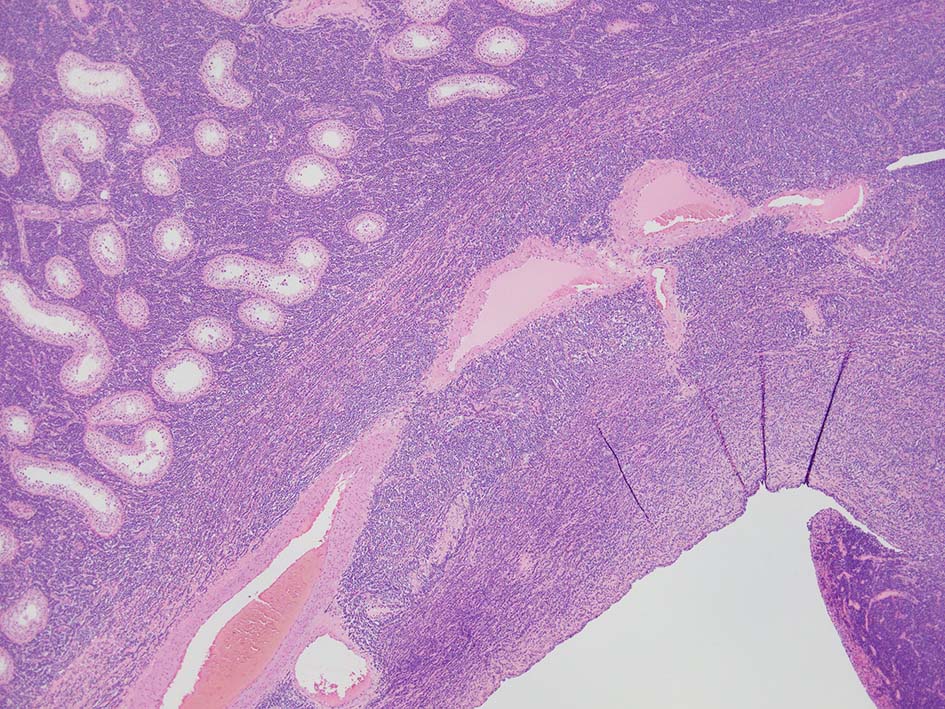

loupe像では, 腫瘍細胞が髄様密に浸潤増殖する部位と, 精細管をスペアするように管間に腫瘍細胞が浸潤する部分(右端図 A)がある.

切り出し図とは天地を逆にした右端図では, 髄様密な部分は白膜内で増殖するリンパ腫瘤(B)であることがわかる. 精巣上体の一部に浸潤がみられる(C)